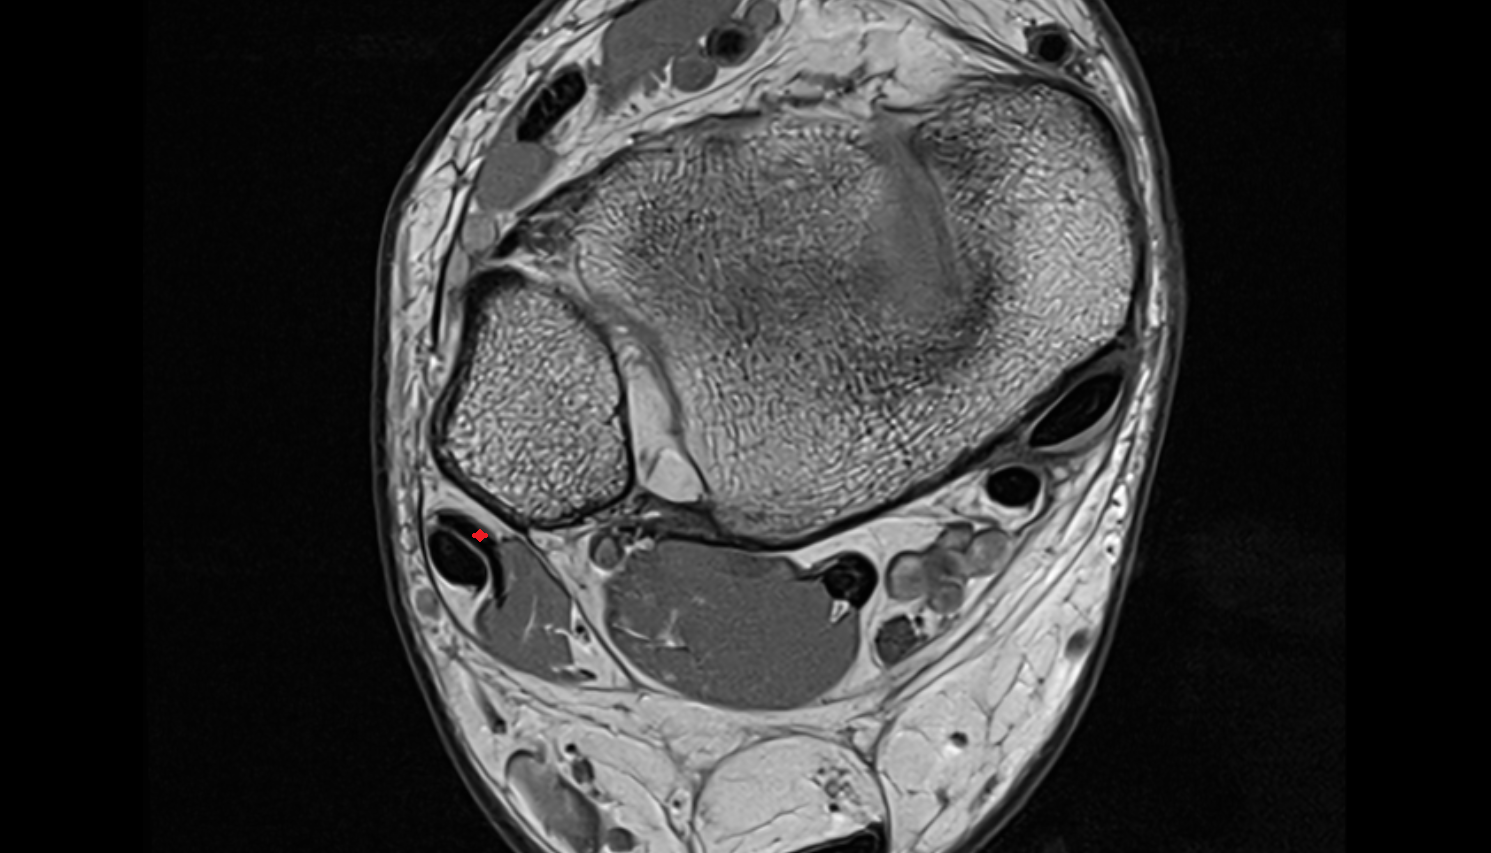

- Articular disc of temporomandibular joint

- Intermediate zone of articular disc

- Lateral temporomandibular ligament

- Superior retrodiscal layer

- Superior synovial membrane of temporomandibular joint

- Mandibular condyle

- Mandibular fossa